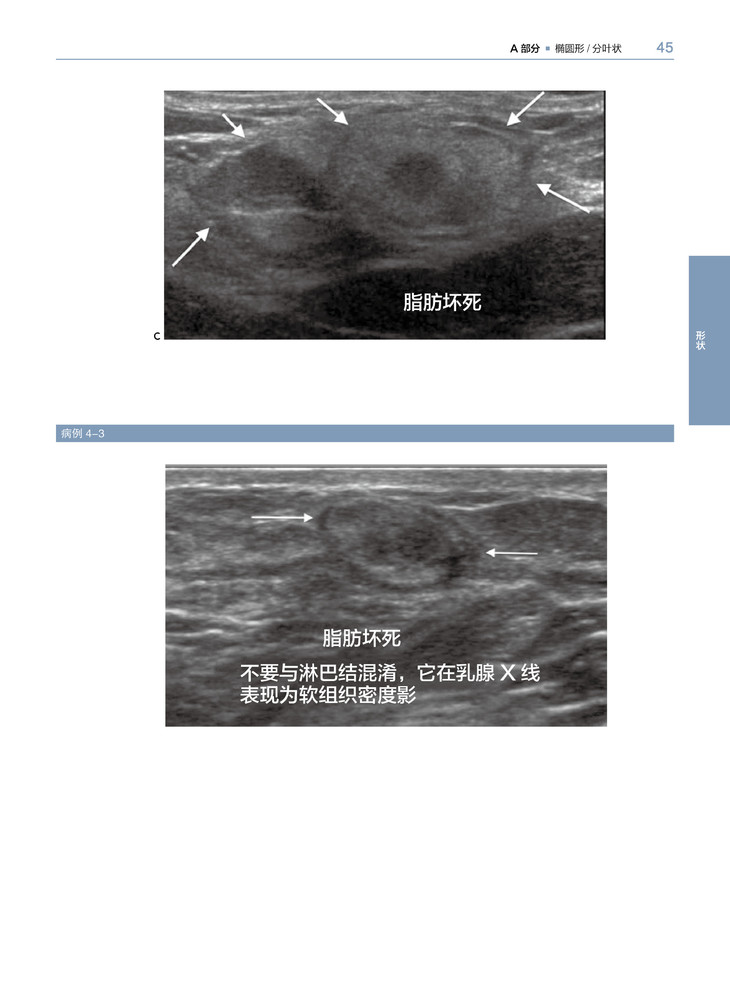

1.这本图集通过乳腺X线摄影或超声图像解释了乳腺影像 “怎样形成”和“为什么形成”的问题。应用病例优先选择的模式与你讲述了大量的常见和不常见的影像图像,与病理相结合阐述结果,帮助读者建立分析病例的能力,这样可以在诊断乳腺病例时信心十足。

2.对病例认识能力的提高,有赖于对病理描述分类的识别(例如肿块、钙化、结构扭曲等等及不太常见的恶性特征),而不是最后的病理诊断。

3.学习应用形状和边界去评估肿块,应用形态和分布去评估钙化,从重叠组织中辨别结构扭曲。领会如何应用大部分特征鉴别良性与恶性的可能性。

乳腺X线摄影和超声影像是乳腺影像检查最常用的两种方法。本书针对临床经常出现的有关乳腺癌影像表现,进行全面分析、归纳。乳腺癌主要是以三种形式表现的:肿块、钙化和结构变形。这本书主要分成以上3个主要部分,第四部分主要包括一些与恶性乳腺癌相关的重要影像表现。全书以病例为主,一共有400多个病例,文字简练,图片清晰,有病例的影像检查图,病理图,代表性强,能为各级影像科、乳腺科医生提供宝贵的参考价值。